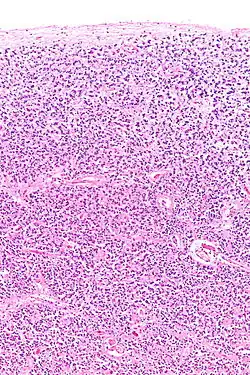

The pineal body in humans consists of a lobular parenchyma of pinealocytes surrounded by connective tissue spaces. The gland's surface is covered by a pial capsule.

The pineal gland consists mainly of pinealocytes, but four other cell types have been identified. As it is quite cellular (in relation to the cortex and white matter), it may be mistaken for a neoplasm.[18]

| Pinealocytes | The pinealocytes consist of a cell body with 4–6 processes emerging. They produce and secrete melatonin. The pinealocytes can be stained by special silver impregnation methods. Their cytoplasm is lightly basophilic. With special stains, pinealocytes exhibit lengthy, branched cytoplasmic processes that extend to the connective septa and its blood vessels. |

| Interstitial cells | Interstitial cells are located between the pinealocytes. They have elongated nuclei and a cytoplasm that is stained darker than that of the pinealocytes. |

| Perivascular phagocyte | Many capillaries are present in the gland, and perivascular phagocytes are located close to these blood vessels. The perivascular phagocytes are antigen presenting cells. |

| Pineal neurons | In higher vertebrates neurons are usually located in the pineal gland. However, this is not the case in rodents. |

| Peptidergic neuron-like cells | In some species, neuronal-like peptidergic cells are present. These cells might have a paracrine regulatory function. |